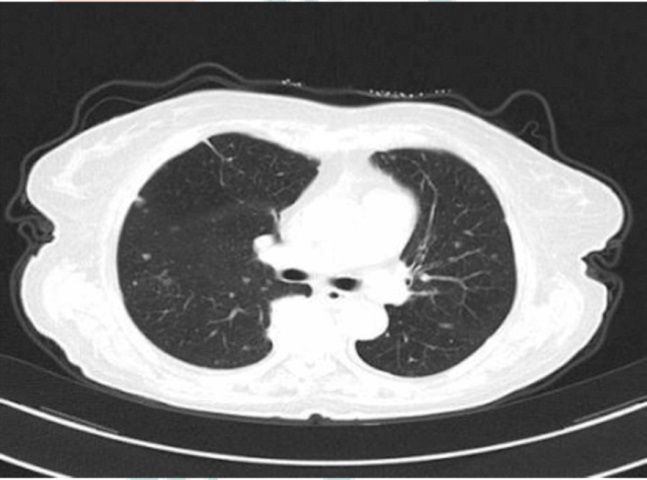

气球状细胞黑色素瘤(BCM)是原发性皮肤黑色素瘤中罕见的组织学类型,文献报道极少,现报道BCM肝转移患者1例,通过介绍该患者的临床病理资料,并观察其组织学形态及免疫表型特征,提升临床医师和病理科医师对此类皮肤转移癌的早期诊断及治疗水平,减少误诊和漏诊。